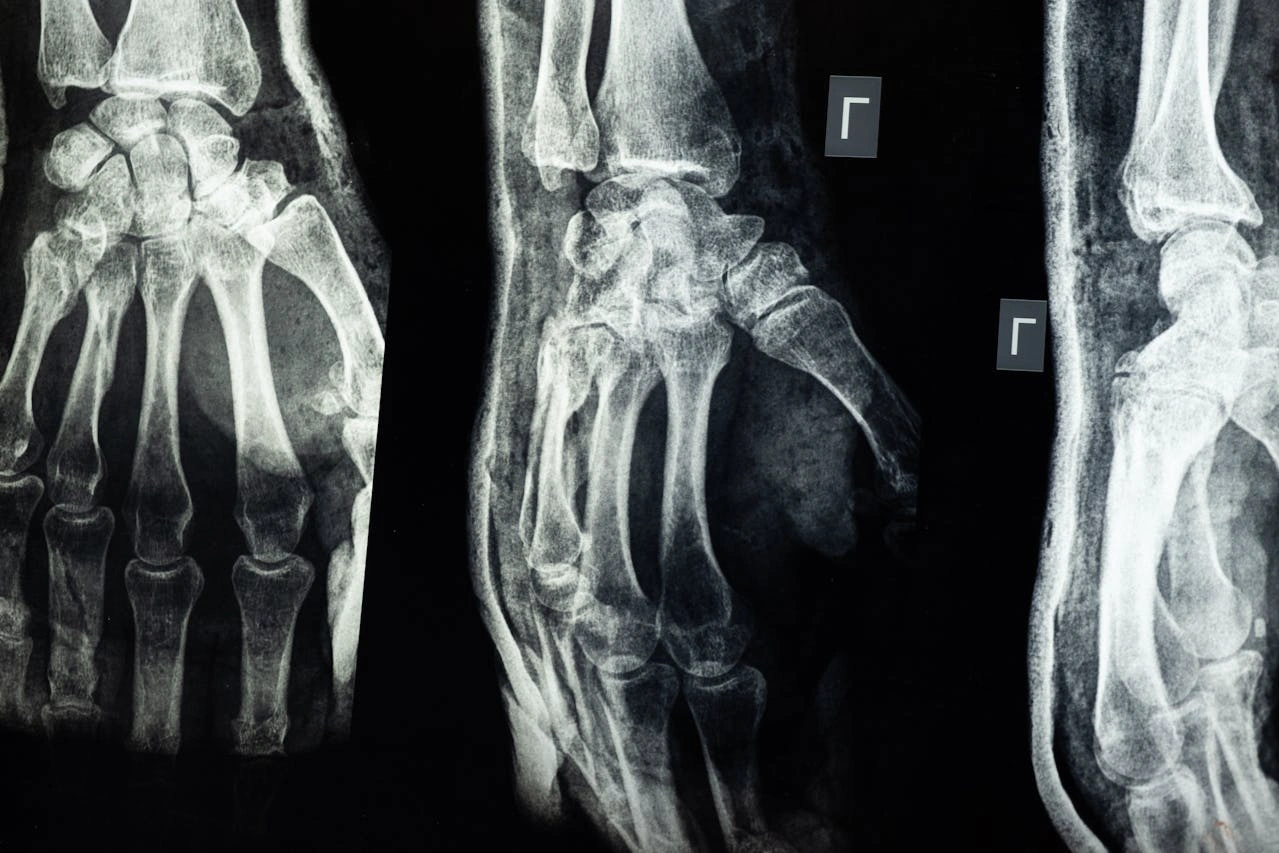

Contohnya adalah sendi-sendi kecil di pergelangan tangan dan kaki yang memungkinkan gerakan geser.

Contohnya adalah sendi pergelangan tangan yang memungkinkan gerakan melengkung ke berbagai arah, tapi tidak sepenuhnya berputar.